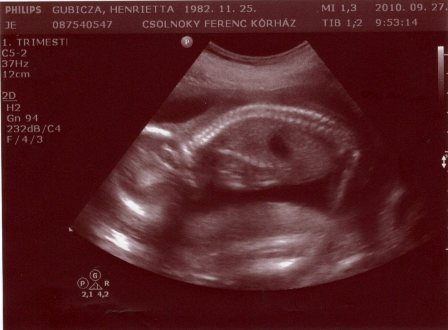

Sziasztok Lányok!

Túl vagyok az UH-n! Minden a legnagyobb rendben van! És igen, hivatalosan is betöltött 12 hetesek vagyunk! :) A vizsgálat kellemetlensége ellenére, csodás érzés volt látni őt, és hallani, ahogy dobog a pici szíve! Talán mivel ez volt az első alkalom, hát könnyek szöktek a szemembe a boldogságtól! Próbálok csatolni képet, de sajnos elég rossz, mert nem volt jó a nyomtató, :( és gyűrte a papírt, de a lényeg talán látható rajt!

Kép